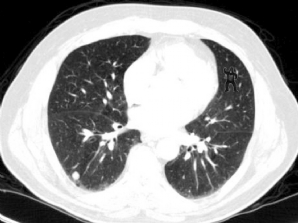

CASO CLÍNICO #30

Na investigação de nódulos pulmonares, 83% dos radiologistas erraram a interpretação dessa tomografia. O que você vê nesse corte tomográfico? Escreva abaixo sua interpretação. ***** In the investigation of pulmonary nodules, 83% of radiologists were wron...